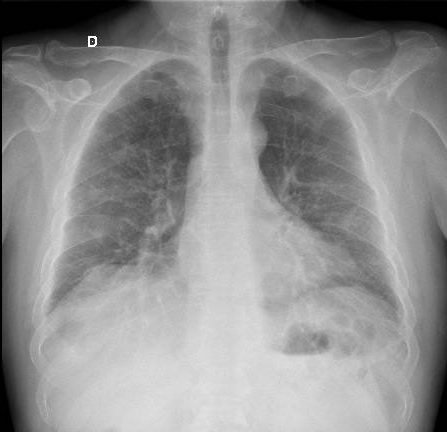

Radiografia de Tórax